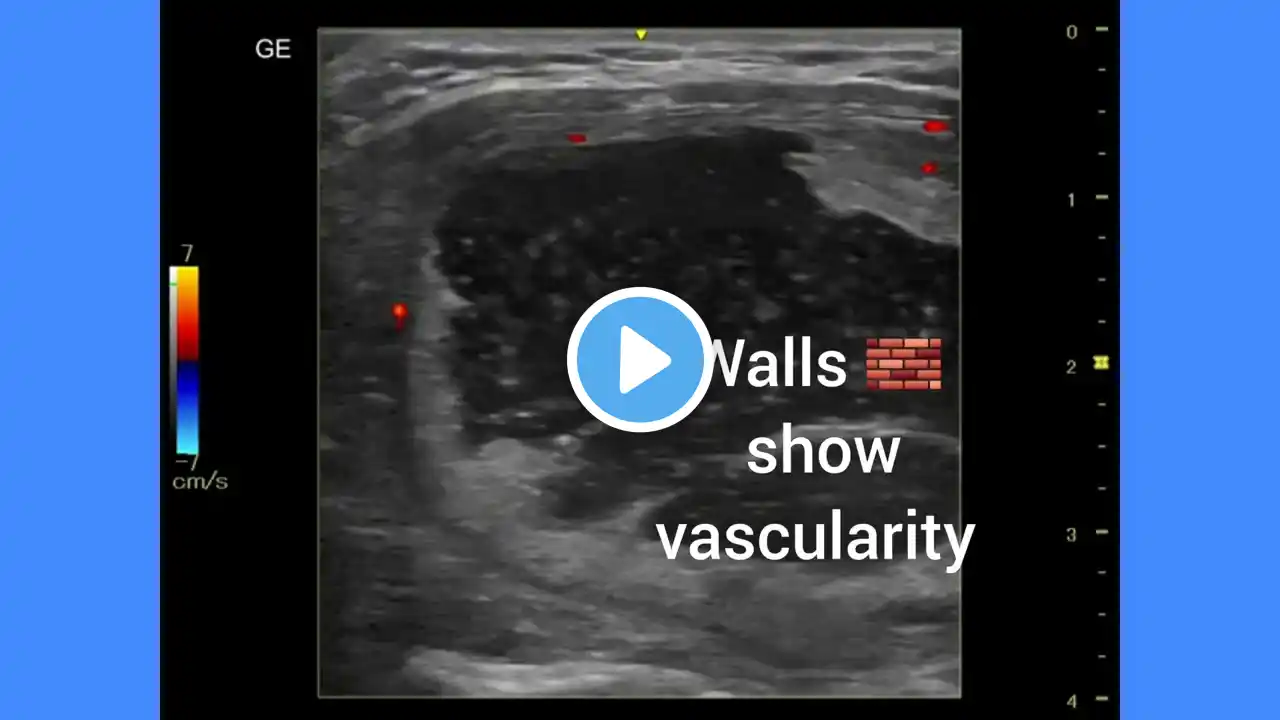

“Sonographic Findings in Hypothyroidism | Thyroid Nodules & Differential Diagnosis” Findings Thyroid gland: Right lobe: Mildly enlarged (44.5 × 16.1 × 19.3 mm). Left lobe: Mildly enlarged (43.4 × 13.3 × 17.5 mm). Isthmus: Normal thickness (3.2 mm). Lesions: Bilateral multiple complex nodules of varying echogenicity and morphology. Some nodules are homogeneous hypoechoic, round to oval with thin halo. Some nodules are hyperechoic with thick peripheral halo. Some nodules are complex with internal cystic component. No obvious extrathyroidal extension or suspicious cervical lymphadenopathy noted. IMPRESSION Multinodular goiter with variable sonographic appearances of nodules. Features are suggestive of a benign process in majority (halo, cystic degeneration, hyperechoic nodules). However, given heterogeneity, possibility of underlying thyroid neoplasm in one of the nodules cannot be excluded. Correlation with thyroid function tests (T3, T4, TSH) and clinical hypothyroidism status is advised. Differential Diagnosis Multinodular goiter with degenerative changes (most likely). Thyroid adenomas (follicular adenoma – hypoechoic with halo). Hashimoto’s thyroiditis with nodularity (if background hypoechoic parenchyma, heterogeneous texture). Less likely but should be excluded: Papillary thyroid carcinoma (especially if microcalcifications, irregular margins, taller-than-wide shape, increased central vascularity). Follicular neoplasm (if solid hypoechoic with thick halo). Suggestions Correlate with TSH, T3, T4, Anti-TPO antibody to evaluate autoimmune thyroiditis. Consider USG-guided FNAC (fine-needle aspiration cytology) of the dominant or suspicious nodules (especially those with solid hypoechoic appearance, irregular thick halo, or internal microcalcification if present). Follow-up ultrasound in 6–12 months if nodules are stable and benign-appearing. Referral to endocrinologist for comprehensive management of hypothyroidism and further evaluation of nodules. Disclaimer This video is for educational and informational purposes only. It is not a substitute for professional medical advice, diagnosis, or treatment. Always consult a qualified healthcare provider for any questions regarding your health condition. #ThyroidUltrasound #Hypothyroidism #ThyroidNodules #Radiology #UltrasoundReport #Endocrinology #ThyroidCare #MedicalEducation #Sonography #ThyroidHealth thyroid ultrasound, hypothyroidism ultrasound, multinodular goiter, thyroid nodules, complex thyroid nodule, thyroid adenoma, thyroid cancer ultrasound, hashimoto thyroiditis ultrasound, sonography report thyroid, ultrasound case study, thyroid gland imaging, endocrinology case, thyroid radiology, thyroid health, thyroid swelling, ultrasound of thyroid, thyroid diagnosis, ultrasound thyroid nodules, thyroid report example, thyroid usg, thyroid gland enlargement, thyroid complex mass, thyroid lesion ultrasound, benign thyroid nodules, thyroid case discussion, radiology thyroid, usg report thyroid, thyroid mass sonography, thyroid gland sonography, thyroid medical education